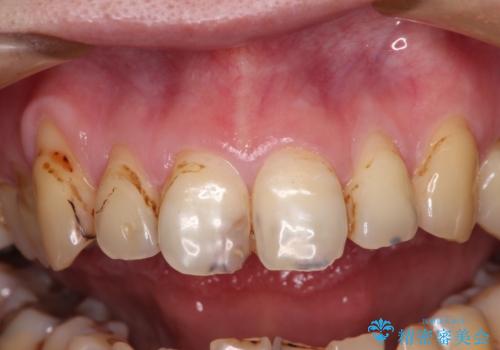

- 前歯のオールセラミック治療を検討しているとのことで来院された患者様です。

前歯は着色や虫歯治療の跡が目立っている状態で、オールセラミッククラウンによる審美治療を希望されていました。

歯肉が非常に菲薄であり、オールセラミッククラウンを装着後の近い将来歯肉退縮によりセラミックの境目が見えてくることが懸念されました。